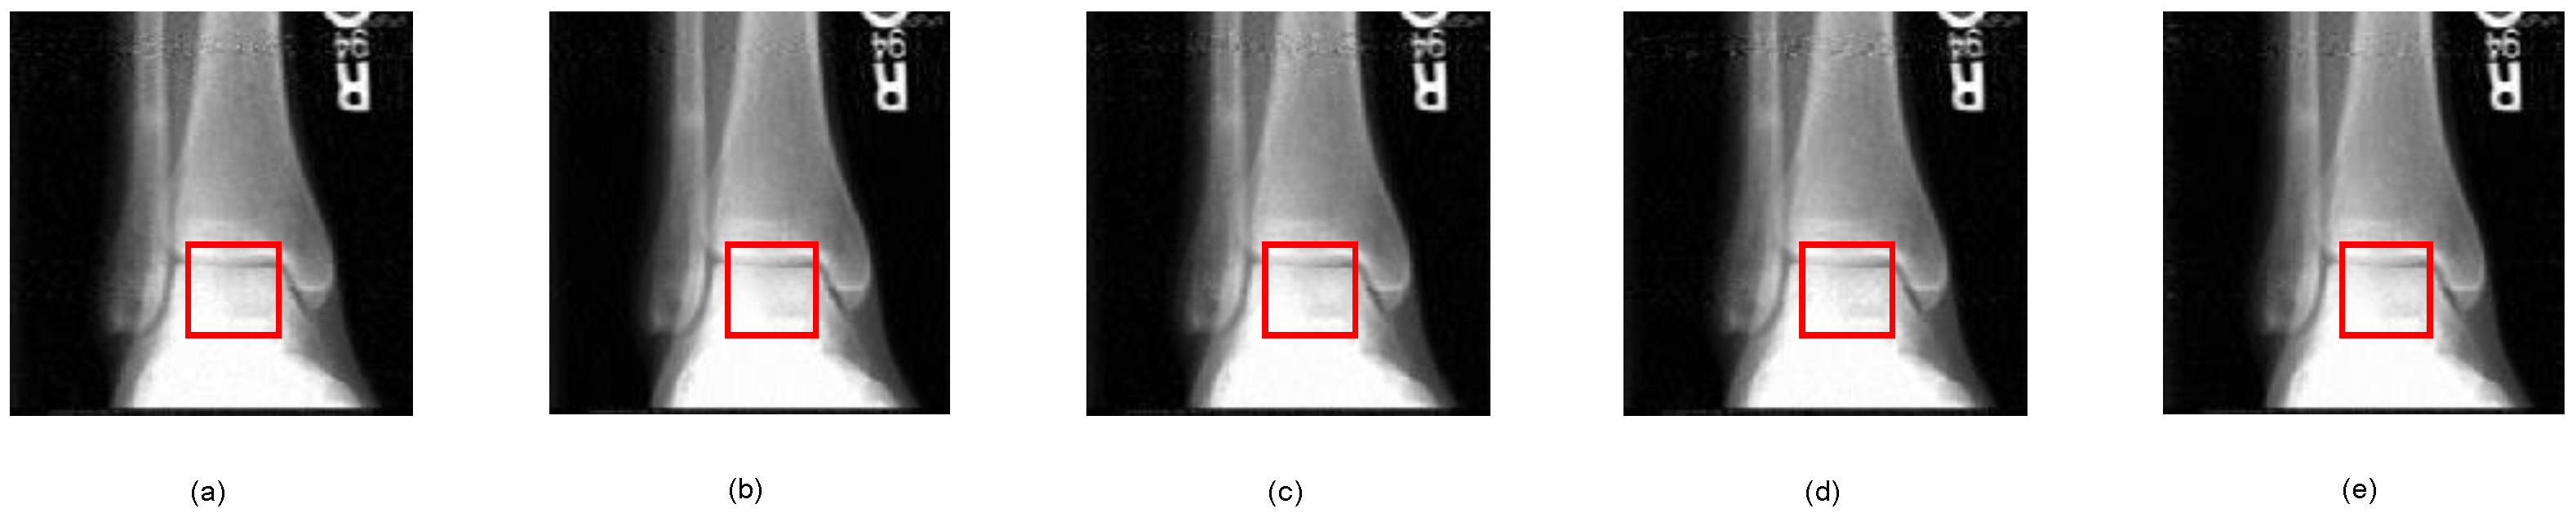

| Bone1 | 33.49 | 31.34 | 31.36 | 31.18 | 30.59 |

| Bone2 | 34.08 | 29.13 | 30.77 | 29.88 | 31.80 |

| Bone1 | 0.935 | 0.889 | 0.894 | 0.897 | 0.897 |

| Bone2 | 0.910 | 0.830 | 0.871 | 0.850 | 0.885 |